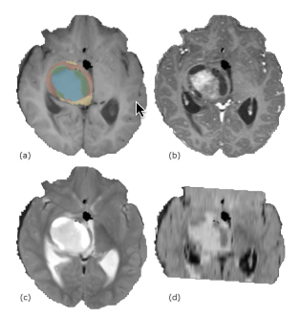

Publication: PLoS One. 2018 Aug 16;13(8):e0202387. PMID: 30114235 | PDF Authors: Reynolds HM, Parameswaran BK, Finnegan ME, Roettger D, Lau E, Kron T, Shaw M, Chander S, Siva S. Institution: Department of Physical Sciences, Peter MacCallum Cancer Centre, Melbourne, Victoria, Australia. Abstract: PURPOSE: To explore the utility of diffusion and perfusion changes in primary renal cell carcinoma (RCC) after stereotactic ablative body radiotherapy (SABR) as an early biomarker of treatment response, using diffusion weighted (DWI) and dynamic contrast enhanced (DCE) MRI. METHODS: Patients enrolled in a prospective pilot clinical trial received SABR for primary RCC, and had DWI and DCE MRI scheduled at baseline, 14 days and 70 days after SABR. Tumours <5cm diameter received a single fraction of 26 Gy and larger tumours received three fractions of 14 Gy. Apparent diffusion coefficient (ADC) maps were computed from DWI data and parametric and pharmacokinetic maps were fitted to the DCE data. Tumour volumes were contoured and statistics extracted. Spearman's rank correlation coefficients were computed between MRI parameter changes versus the percentage tumour volume change from CT at 6, 12 and 24 months and the last follow-up relative to baseline CT. RESULTS: Twelve patients were eligible for DWI analysis, and a subset of ten patients for DCE MRI analysis. DCE MRI from the second follow-up MRI scan showed correlations between the change in percentage voxels with washout contrast enhancement behaviour and the change in tumour volume (ρ = 0.84, p = 0.004 at 12 month CT, ρ = 0.81, p = 0.02 at 24 month CT, and ρ = 0.89, p = 0.001 at last follow-up CT). The change in mean initial rate of enhancement and mean Ktrans at the second follow-up MRI scan were positively correlated with percent tumour volume change at the 12 month CT onwards (ρ = 0.65, p = 0.05 and ρ = 0.66, p = 0.04 at 12 month CT respectively). Changes in ADC kurtosis from histogram analysis at the first follow-up MRI scan also showed positive correlations with the percentage tumour volume change (ρ = 0.66, p = 0.02 at 12 month CT, ρ = 0.69, p = 0.02 at last follow-up CT), but these results are possibly confounded by inflammation. CONCLUSION: DWI and DCE MRI parameters show potential as early response biomarkers after SABR for primary RCC. Further prospective validation using larger patient cohorts is warranted. |

Baseline ADC map with tumour contour in red for patient 3 and associated histogram showing the frequency of ADC values in each MRI scan. ADC maps were read into 3D Slicer software and the tumour volume contoured directly onto ADC map image slices by an experienced radiologist. |